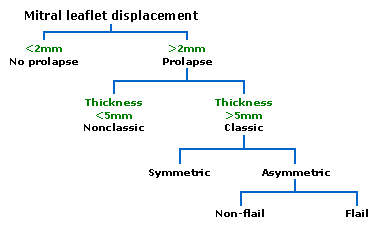

Echocardiography is the most useful method of diagnosing a prolapsed mitral valve. Two- and three-dimensional echocardiography are particularly valuable as they allow visualization of the mitral leaflets relative to the mitral annulus. This allows measurement of the leaflet thickness and their displacement relative to the annulus. Thickening of the mitral leaflets >5 mm and leaflet displacement >2 mm indicates classic mitral valve prolapse.[12]

Prolapsed mitral valves are classified into several subtypes, based on leaflet thickness, type of connection to the mitral annulus, and concavity. Subtypes can be described as classic, nonclassic, symmetric, asymmetric, flail, or non-flail.[12]

Classic versus nonclassic

Prolapse occurs when the mitral valve leaflets are displaced more than 2 mm above the mitral annulus high points. The condition can be further divided into classic and nonclassic subtypes based on the thickness of the mitral valve leaflets: up to 5 mm is considered nonclassic, while anything beyond 5 mm is considered classic MVP.[12]

Symmetric versus asymmetric

Classical prolapse may be subdivided into symmetric and asymmetric, referring to the point at which leaflet tips join the mitral annulus. In symmetric coaptation, leaflet tips meet at a common point on the annulus. Asymmetric coaptation is marked by one leaflet displaced toward the atrium with respect to the other. Patients with asymmetric prolapse are susceptible to severe deterioration of the mitral valve, with the possible rupture of the chordae tendineae and the development of a flail leaflet.[12]

Flail versus non-flail

Asymmetric prolapse is further subdivided into flail and non-flail. Flail prolapse occurs when a leaflet tip turns outward, becoming concave toward the left atrium, causing the deterioration of the mitral valve. The severity of flail leaflet varies, ranging from tip eversion to chordal rupture. Dissociation of leaflet and chordae tendineae provides for unrestricted motion of the leaflet (hence "flail leaflet"). Thus patients with flail leaflets have a higher prevalence of mitral regurgitation than those with the non-flail subtype.[12]